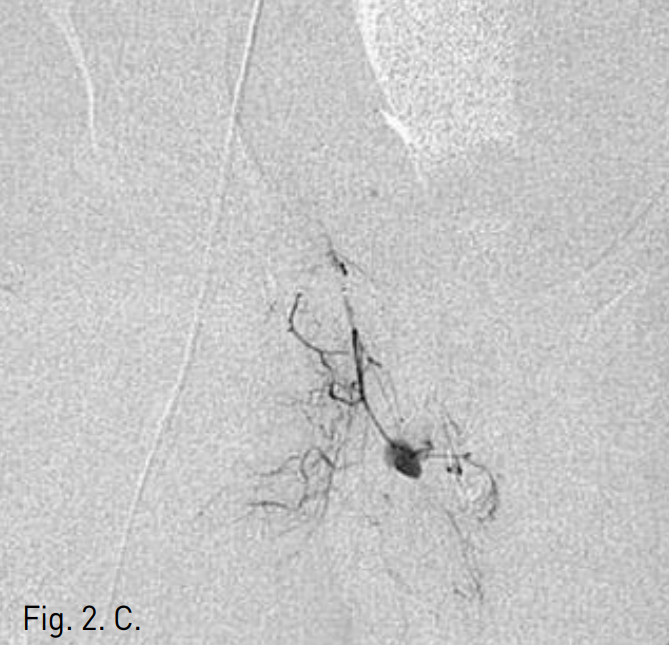

To identify the location of the bleeding site, digital subtraction angiography was performed. Selective angiogram of right common iliac artery showed two contrast extravasations or bleeding points at suprapubic area(Fig. 2A). Selective internal iliac arteriogram showed only one bleeding point from the obturator artery(Fig. 2B). After superselective cannulating into the feeding branch from the obturator artery by using a coaxial microcatheter, embolization was performed with gelfoam particles(Fig. 2C). Follow-up right common iliac angiogram showed persistent contrast extravasation and identified feeding branch of aberrant obturator artery from the inferior epigastric artery(Fig. 2D). Additional selective embolization was performed with gelfoam particles.

Fig. 2

A. Pelvic angiogram shows two contrast extravasations in pubic area (thin arrows). The inferior epigastric artery (thick arrow) and aberrant obturator artery (arrowheads) are noted.

B. Internal iliac arteriogram shows active bleeding from the obturator artery (arrow).

C. Selective embolization of obturator artery from the internal iliac artery was done.

D. Persistent contrast extravasation being fed by aberrant obturator artery (arrows), a branch of inferior epigastric artery, is identified on common iliac angiogram. So additional selective bleeding artery embolization was done.